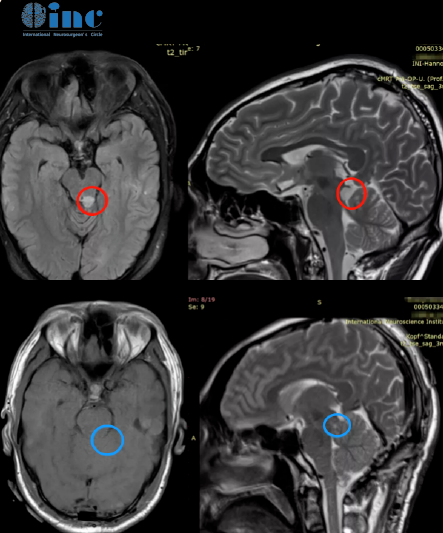

2020年一纸诊断打破了周老师幸福的生活——脑干胶质瘤。就是这个肿瘤,棘手,位置不同,它长在了脑干。虽然肿瘤不大,但手术难度很大,“生命中枢”、“手术禁区”。脑干手术做不好很可能会导致四肢截瘫,甚至不少患者术后躺在ICU里长期昏迷。但不做手术的话,肿瘤会继续长,到时候也不止是头痛、眼痛,还会造成肢体无力,站立不稳,无法独自行走,甚至呼吸控制、昏迷,也同样随时可能危及生命。

历经7个小时的手术,教授在半坐位下,使用,幕下小脑上入路,全切了胶质瘤。术后1天,他就迁出ICU,回到普通病房,呼吸、心率平稳,还能自行用餐,没有,术后并发症。术后2天,开始进行,康复训练;术后5天,周老师就出院了。在平安夜,周老师从法兰克福启程回国,寓意往后都“平平安安”……